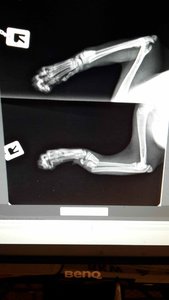

Mein größtes Sorgenkind, aber ein Kämpfer.

Aber wirklich. Beeindruckend, wie er da herummarschiert. Wird das Beinchen wieder?

Wir hoffen es, er wurde in der Tierklinik operiert. Wenn ich hier richtig durchgeblickt habe erzähle ich mehr von ihm.IMG-20180928-WA0018.jpeg